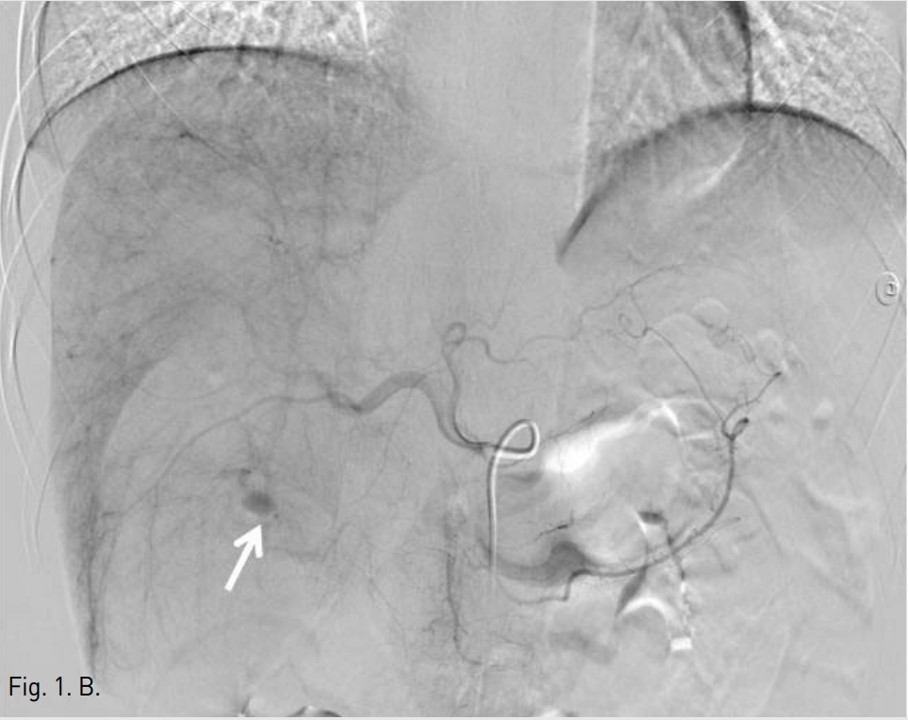

Fig. 1. B

Fig. 1B. Celiac angiogram shows active bleeding (arrow) from a branch of the right hepatic artery. After selective catheterization of the bleeding artery with a 2.9 F microcatheter, the artery was embolized by using gelatin sponge.

5F RH catheter (Cook, Bloomington, USA)를 이용하여 바로 시행한 간동맥조영술에서 right posterior inferior hepatic branch에서 급성출혈이 관찰되었다(Fig. 1B). 2.9F coaxial microcatheter(Stride, ASAHI, Aichi, Japan) 로 출혈혈관부위를 초선택한 후 gelatin sponge(Cutanplast, Mascia Brunelli , Milan, Italy)을 이용하여 색전술을 시행하였다(Fig. 1C). 시술 다음날 혈색소 수치는 10.0g/dL로 증가하였다. 그러나 시술 2일 후 환자의 활력징후는 혈압 131/80mmHg, 맥박수 82/min로 안정적이었지만, 혈색소가 7.8g/dL로 급격히 감소하였고, 우상복부에 심한 통증을 호소하여 재출혈의 의심하에 복부 CT검사를 시행하였다. CT검사에서 간에 다량의 피막하 혈종이 관찰되었지만, 조영제의 혈관외 유출은 보이지 않았다(AAST grade Ⅲ)(Fig. 2A). 같은 날 시행한 간동맥 혈관조영술에서 기존 색전술을 시행한 동맥에서의 재관류는 없었지만, 새로 생긴 다른 부위의 피막하혈종 내로 광범위한 다발성 미세출혈이 관찰되었다(Fig. 2B). Microcatheter를 이용하여 각 출혈부위 근처의 segmental artery들을 선택한 후 gelatin sponge를 이용하여 광범위한 부위에 색전술을 시행하였고, 더 이상의 출혈은 관찰되지 않았다(Fig. 2C, D). 시술 후 환자의 혈색소는 정상화되었고 우상복부 통증은 점차 감소하였다. 이 후 뚜렷한 합병증 없이 입원 1달 후 퇴원하였다.